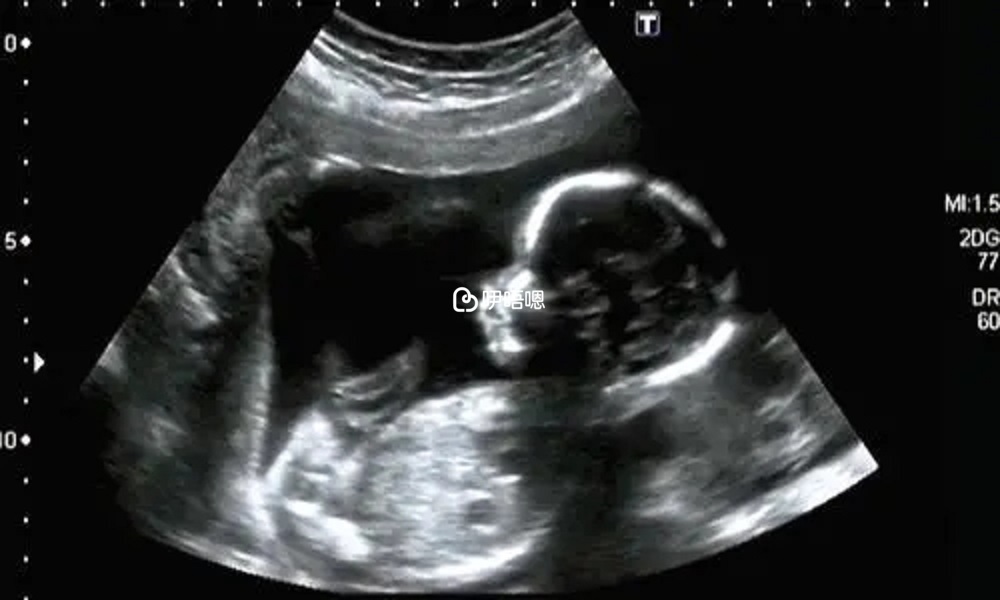

一超檢查時間在開獎的三週後,即孕6-7周,主要檢查胎兒是否有卵黃囊胎心胎芽!我們試管的是在移植完的第十四天去抽血看hcg值,如果值達到一定數,醫生就會恭喜我們,此處如果準媽媽們要注意)有很多一超看不到雙胎的,在二超甚至NT的時候才會檢查出來。

我當時hcg就比較高,問大夫有沒有可能是hcg,大夫說你這個可能性不大,因為是囊胚所以值高一些!二超檢查時間在一超的三週後,孕9周左右。